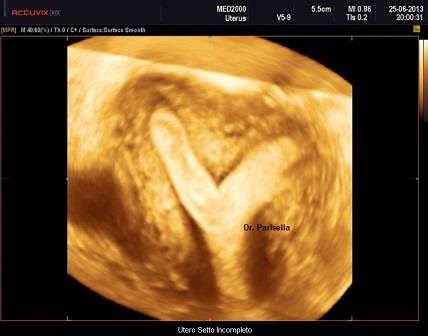

Utero Setto

E' la malformazione uterina più frequente (55% delle anomalie mulleriane); è la conseguenza di un incompleto riassorbimento del setto uterovaginale dopo la fusione dei dotti di Muller.

Ecograficamente è fondamentale la visualizzazione del profilo del fondo uterino per differenziarlo dall'utero bicorne. Nell'utero setto il profilo del fondo può essere convesso, appianato o a volte concavo. L'eco 3D, permettendo una accurata scansione coronale consente, nella maggior parte dei casi, di poter differenziare questa anomalia dall'utero bicorne.

Si distinguono due tipi di utero setto:

- utero setto completo: il setto si estende dal fondo alla cervice

- utero setto incompleto: il setto origina dal fondo e non giunge all'OUI.

L'Utero setto può associarsi a varie complicanze ostetriche:

- aborti nel I e nel II trimestre

- parti pretermine

- anomalie di posizione fetale

- ritardo di crescita fetale

L'utero setto è facilmente correggibile per via isteroscopica.